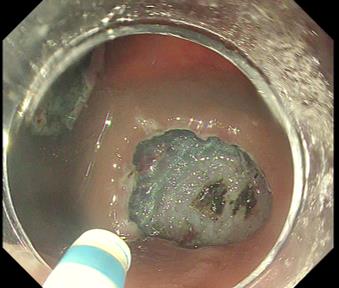

Using DualKnife J’s jet function

Movie 4 : Tips for mucosa lifting

In cases with fibrosis, the knife’s jet function is particularly useful. Fig. 10 shows a mid-procedure phase in which the fibrotic region has been exposed by digging on both sides. Because secure preservation of the dissection space is desirable at this stage, the usual approach is to switch devices and insert a local injection needle. However, changing devices takes time, and it is not uncommon for the field of view to change during that interval. Instead, using the DualKnife J’s jet function allows you to proceed rapidly with dissection while delivering fluid.

When local injection is performed with a needle, the submucosal cushion may dissipate when the device is switched to the knife. The jet function, on the other hand, makes it possible to start dissection at the exact moment the submucosal layer is elevated.

The procedure to use the jet function is simple: 1) Retract the tip; 2) Lightly touch the target area with the sheath tip to deliver the liquid press the coagulation wave pedal on the electrosurgical unit; 3) Project the knife tip; 4) Start the jet function through the knife.

This enables effective elevation of the submucosal layer. Efficient delivery is also possible by connecting a water-jet pump to the knife. If delivering saline, you can attach a 5–10 cc syringe externally to the knife and push by hand (Fig. 11).